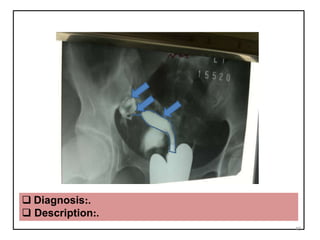

 Diagnosis:.

 Description:.